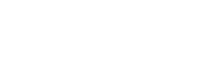

Patient had a 3 unit bridge that was decayed. A CT scan was taken to evaluate the surrounding bone. Patient underwent extraction and Bone Grafting to regenerate and build the necessary bone for implant placement. Implant was placed. Final x-ray showing 3 implants placed to replace the bridge.